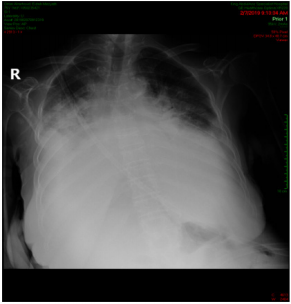

A 88-years old female with remarkable history for diabetes, ischemic heart disease, known case of CML for which she received imatinib for more than 10 years and still under treatment. This patient presented with two weeks history of gradually progressive breathlessness, mild cough associated with LL swelling and not associated with fever. The patient came to emergency department where ECG and echocardiography were normal apart from mild to moderate pericardial effusion, X-ray chest showed bilateral moderate pleural effusion (Figure 1) then patient was admitted for further evaluation and management. We asked for full investigations, CT chest showed moderate bilateral effusion more in the left side (Figure 2A) with mild pericardial effusion (Figure 2B), abdomino-pelvic ultrasound showed normal abdominal and pelvic organs with moderate free fluid in abdomen and pelvis, complete blood count, renal function tests, liver function tests and serum electrolytes are all within normal limits. Aspiration of both ascetic and pleural fluids was done and subjected to chemical, microbiological and cytological analysis which showed features of transudate with no growth of any organism. So based on history, clinical examination and investigations, all causes of generalized edema were excluded and the only explanation for development of this generalized FR was imatinib use. As the patient was in hematological and molecular complete response(CR) for last year, we stopped the imatinib and the patient was followed and treated symptomatically. We expected that the conditions of the patient will improved after imatinib withdrawal and diuretics, but there is no improvement after more than 3 weeks of stoppage of imatinib.